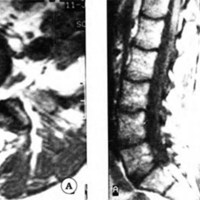

CASO 3

Paciente mujer de 56 años con severa lumbociatalgia derecha y signos de compresión radicular L5 derecha. La TAC mostró una lesión yuxtaarticular L4-L5 derecha, de bordes netos e hiperdensos y centro hipodenso. La IRM mostró una imagen hipointensa en T1 e hiperintensa en T2 que desplaza al saco dural (Fig. 3). Se realizó la exéresis por vía posterior confirmando la histología el diagnóstico de QS.

Fig 3. Caso 3